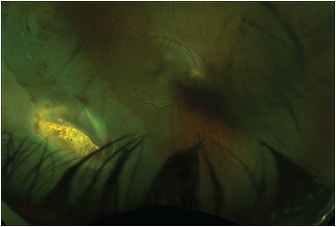

The posterior segment should be evaluated for an IOFB (Figure 3), which can be located in the vitreous, ciliary body, retina, choroid, or the posterior sclera. The posterior segment should be evaluated for traumatic posterior segment pathology such as vitreous hemorrhage, commotion, retinal tears, retinal detachment (Figure 4) or dialysis, choroidal detachment, choroidal rupture, sclopetaria, and a posterior exit wound. Dense vitreous hemorrhage or cataracts can preclude visualization of the posterior segment, so imaging modalities might be needed to identify an IOFB. In eyes that do not permit a clear view of the posterior segment, the presence of a metallic IOFB can be confirmed using a metal detector.